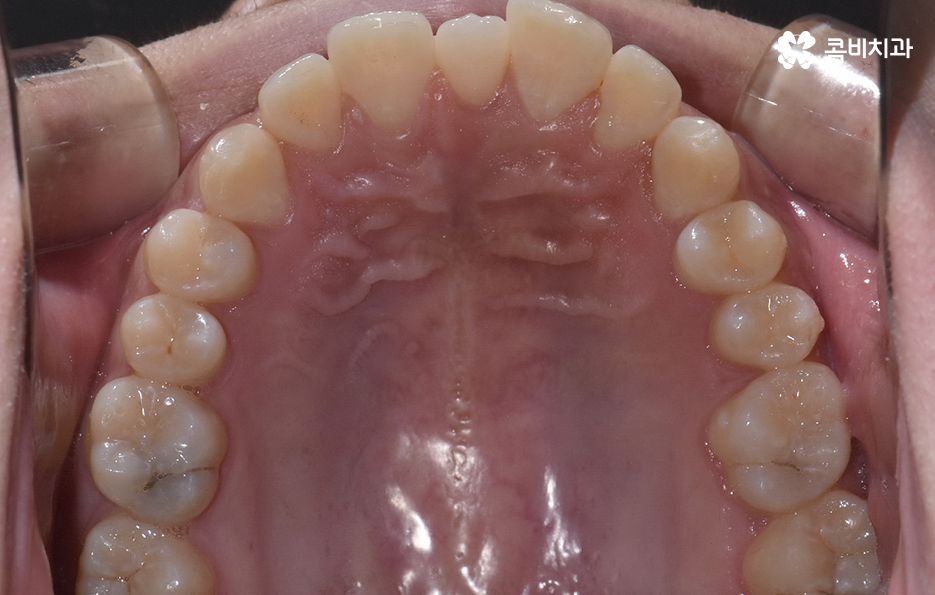

과잉치 중에서는 어떤 치아가 과잉치인지 구분이 어려울 정도로 일반적인 정상 치아의 크기와 비슷한 크기와 형태를 띄는 경우도 있는 반면에 위 사진의 케이스는 첫번째 앞니와 앞니 사이에 유독 작은 왜소치가 있는 형태이기 때문에 치아의 기능적인 문제 보다는 심미적인 개선을 필요했던 케이스로 볼 수 있어요

그나마 다행인 점은 앞니만교정을 하더라도 치아의 교합이나 골격적인 부분, 얼굴형 등에 있어서 큰 지장은 없던 경우였는데요. 물론 아랫니가 다소 벌어져 있기 때문에 전체교정을 하면 더 좋은 결과를 얻을 수 있었겠지만 환자분의 니즈에 있어서 앞니만교정을 빠르게 원했던 사례이기 때문에 앞니 부분의 과잉치 발치 후 앞니만교정을 부분적으로 진행했어요

과잉치로 인해 말그대로 치아의 정상 범위 이상으로 치아가 배열되기 때문에 다른 치아의 배열에도 악영향을 주는 경우가 많지만 위 환자분의 케이스의 경우에는 치열 자체는 전체적으로 가지런한 편이라는 점과 특히 턱뼈가 넓은 편이라는 점에서 전체교정을 하지 않았어도 환자분이 원하는 치료의 목표는 달성할 수 있었어요